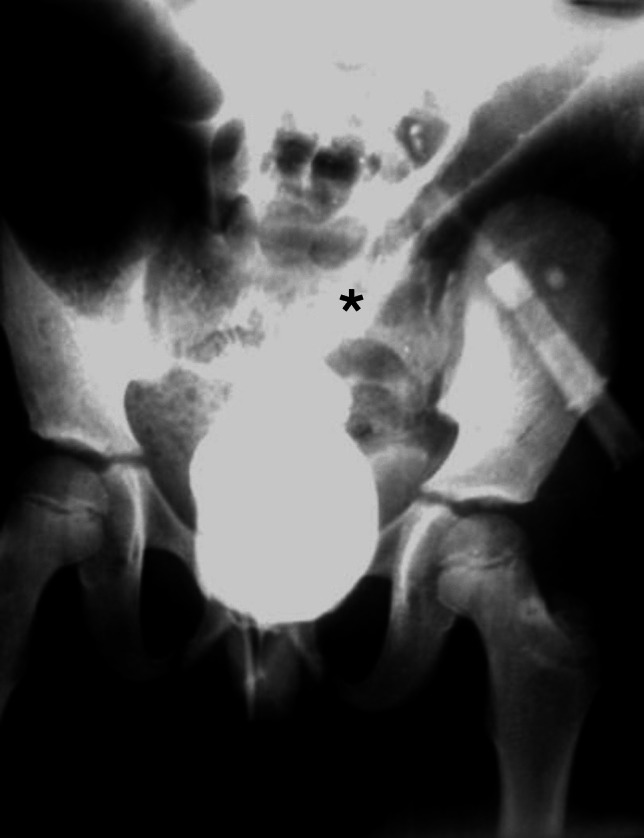

Purpose: Colonic volvulus (CV) is a twist of part of the colon over its mesentery. Although CV is rare in children, its incidence is unknown. Hirschsprung's disease (HD) represents a significant risk factor of CV in children, especially when diagnosed late.

Aim: To review the clinical, radiological and management data of children with CV associated with HD.

Methods: Medical records were reviewed from January 2000 to December 2022 looking for children had CV associated with HD.

Results: 21 cases (17 males and 4 females) were admitted with CV. Their ages ranged from 8 days to 14 years. Sigmoid volvulus was recorded in 17 (81%) cases, while 4 (19%) cases had cecal volvulus. CV was associated with HD in 9 (42.9%) cases. Their median age was 7 years. Eight cases had sigmoid volvulus associated with short segment HD, while one case had cecal volvulus with long segment HD. CV was the first presentation, before the diagnosis of HD, in 8 cases. The diagnosis of HD was overlooked in 3 cases; 2 cases had an anastomotic leakage after sigmoidectomy, while the third case had recurrence of volvulus after successful nonoperative management.

Conclusion: The diagnosis of CV in children mandates a high index of suspicion. Moreover, HD should be suspected and excluded in every case of CV in children.